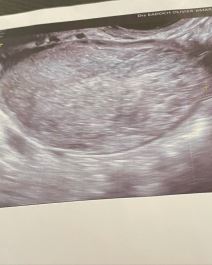

Podelila je fotografije u bolničkoj spavaćici i sliku sa ultrazvuka, objašnjavajući da je bol ponovo počela tri meseca nakon prve operacije.

"Dan nakon toga sam imala zakazan pregled kod jednog neverovatnog lekara koji je odmah uočio da imam cistu od 5,6 cm koja dodiruje moj jajnik. Poslao me je da uradim magnetnu rezonancu i sat vremena kasnije me je pozvao i rekao da odmah idem u bolnicu na hitnu operaciju."